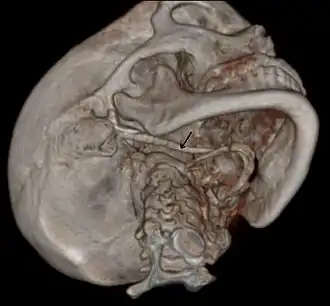

3D-reconstructed CT scan showing bilateral stylohyoid ligament ossification -

Imaging is important and is diagnostic. Visualizing the styloid process on a CT scan with 3D reconstruction is the suggested imaging technique.[13] The enlarged styloid may be visible on an orthopantogram or a lateral soft tissue X ray of the neck.